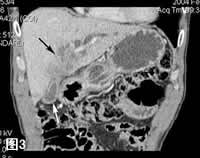

图3:肺门前水平冠状MPR(多层重组)像,示肿瘤发生于肝左叶肝管内,远侧肝管分支扩张。